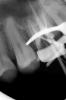

Каплан Опубликовано 3 апреля, 2013 Поделиться Опубликовано 3 апреля, 2013 (изменено) длина 26. 25.06 до упора (примерно 20), потом померил, 10.04, 20.06, 30.05 на 23.5 мм, апикальную треть 35.02 и 40.02 руками...через кальций, потому что не было времени.во второй визит 35.04 на длину 25, и 40.02 на всю рд.обтурировал, немного насвинячил за апексом...http://img442.imageshack.us/img442/1084/27581793.jpg Uploaded with ImageShack.us Изменено 3 апреля, 2013 пользователем Каплан 3 Ссылка на комментарий